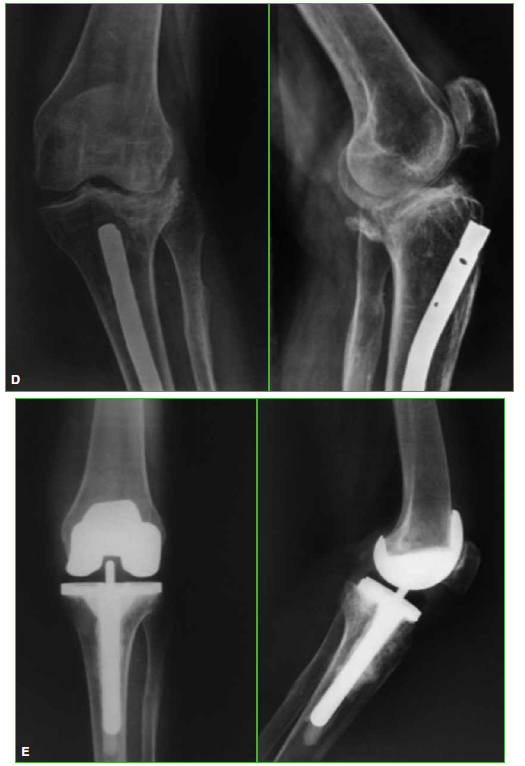

Figura. A.

Mujer con fractura de platillo tibial externo tratada con osteosintesis. B. Fractura de tibia distal, un año despues. C. Osteosintesis con clavo anterogrado endomedular de tibia.

Figura. D.

Retiro de tornillos canulados y toma de muestra, a los 4 meses. E. Artroplastia total de rodilla izquierda, con vastago tibial.